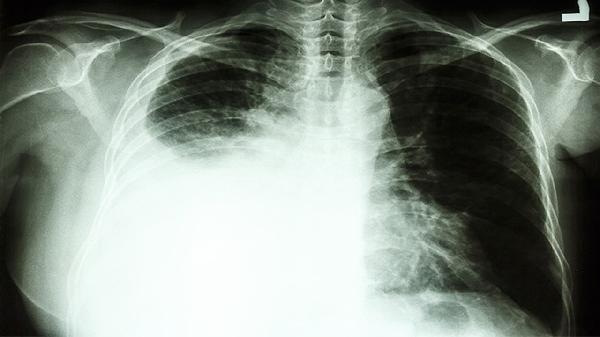

肺部肿瘤占位影响气体交换时,动脉血氧分压下降可致脑缺氧性头晕。患者多伴有呼吸困难、口唇发绀。可通过吸氧改善症状,同时使用注射用培美曲塞二钠、卡铂注射液等化疗药物控制肿瘤进展。

肺癌患者出现头晕时应卧床休息避免跌倒,保持环境通风。饮食需增加瘦肉、动物肝脏等富含铁的食物,限制每日饮水量以防加重低钠血症。定期监测血常规、血气分析及电解质指标,若头晕持续或加重需立即复查胸部CT排除脑转移。治疗期间避免突然改变体位,起身时动作宜缓慢。